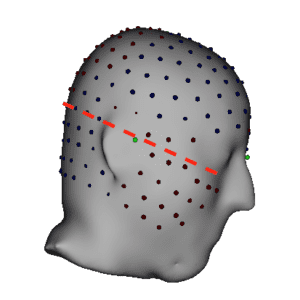

In contrast, high density EEG (128 – 256 electrodes) covers area on the scalp well below the canthomeatal line as shown in the image below:

A recent study from the University of Geneva shows this to be important for capturing activity originating from lower brain regions.